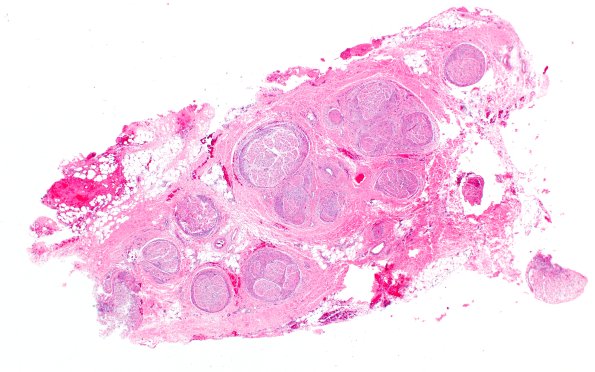

Washington University Experience | PERIPHERAL NEUROPATHY | 19 TRAUMATIC INJURIES | 25A1 Nerve Trauma (Case 25) H&E 2X

Although this is a traumatic lesion, one feature of the histology is unusual in my experience and bears comment. An unusual appearance for a “traumatic neuroma” is this cross section of multiple fascicles in which many fascicles are completely surrounded by an impressive thick proliferation of circularly oriented cells. (H&E)